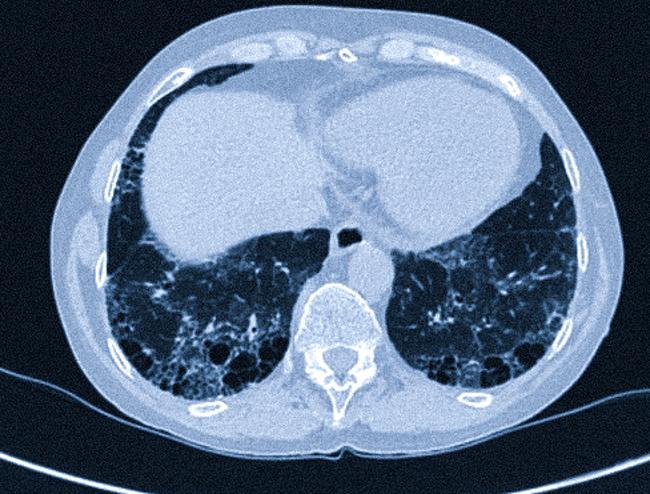

В третьей фазе развивается отек легкого с последующим разрастанием фиброзной ткани. На томограммах видно утолщение межальвеолярных перегородок, дающее картину хаотичной исчерченности. Снижается пневматизация паренхимы. Характерным симптомом фиброзных изменений является «сотовое легкое».

Симптом «матового стекла»